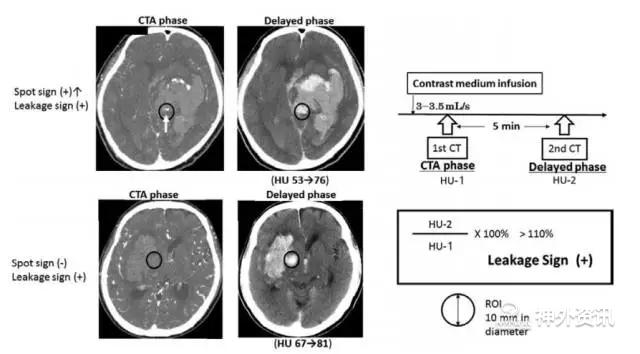

研究纳入80例原发性脑出血患者,其中男性38例,女性42例;平均年龄67.9±12.9岁。血肿位于基底节(45%)、丘脑(35%)、脑叶(11.3%)、脑干(10%)和小脑(8.7%) 。所有患者均行CTA检查,并在CT造影结束后五分钟再行一次CT平扫;然后将动脉相和延迟相病灶周围宽1cm的区域作为考察区(ROI),分析动脉相和延迟相在考察区内的HU值前后变化;HU增加>10%视为“渗漏征”阳性(图1)。

图1. 脑出血患者渗漏征的判断标准。在动脉相和延迟相上,标出血肿周围一宽为1cm的观察区(ROI)。分别测量动脉相和延迟相ROI区的HU值,HU增加>10%视为渗漏征阳性。